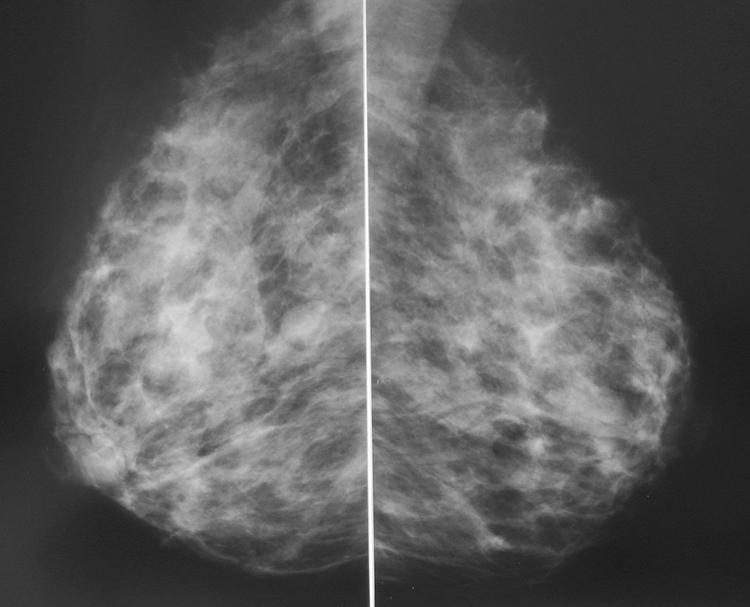

Что такое маммография: важность, процесс и результаты